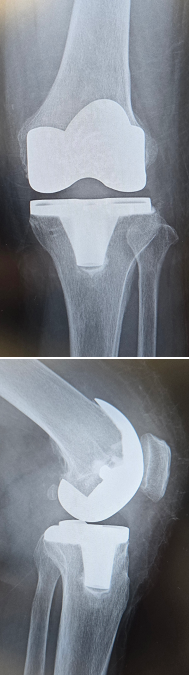

当院にて両側の人工ひざ関節全置換術(TKA)を施行。

高度のO脚変形があり、歩行時のひざの不安定感も強い症例です。

キネマティックアライメント法で手術を行いました。

キネマティックアライメントとは、ひざ本来の靭帯のバランス、下肢の形を取り戻すことに重点を置いた方法です。

〈手術後のレントゲン〉

〈下肢全長の変化〉